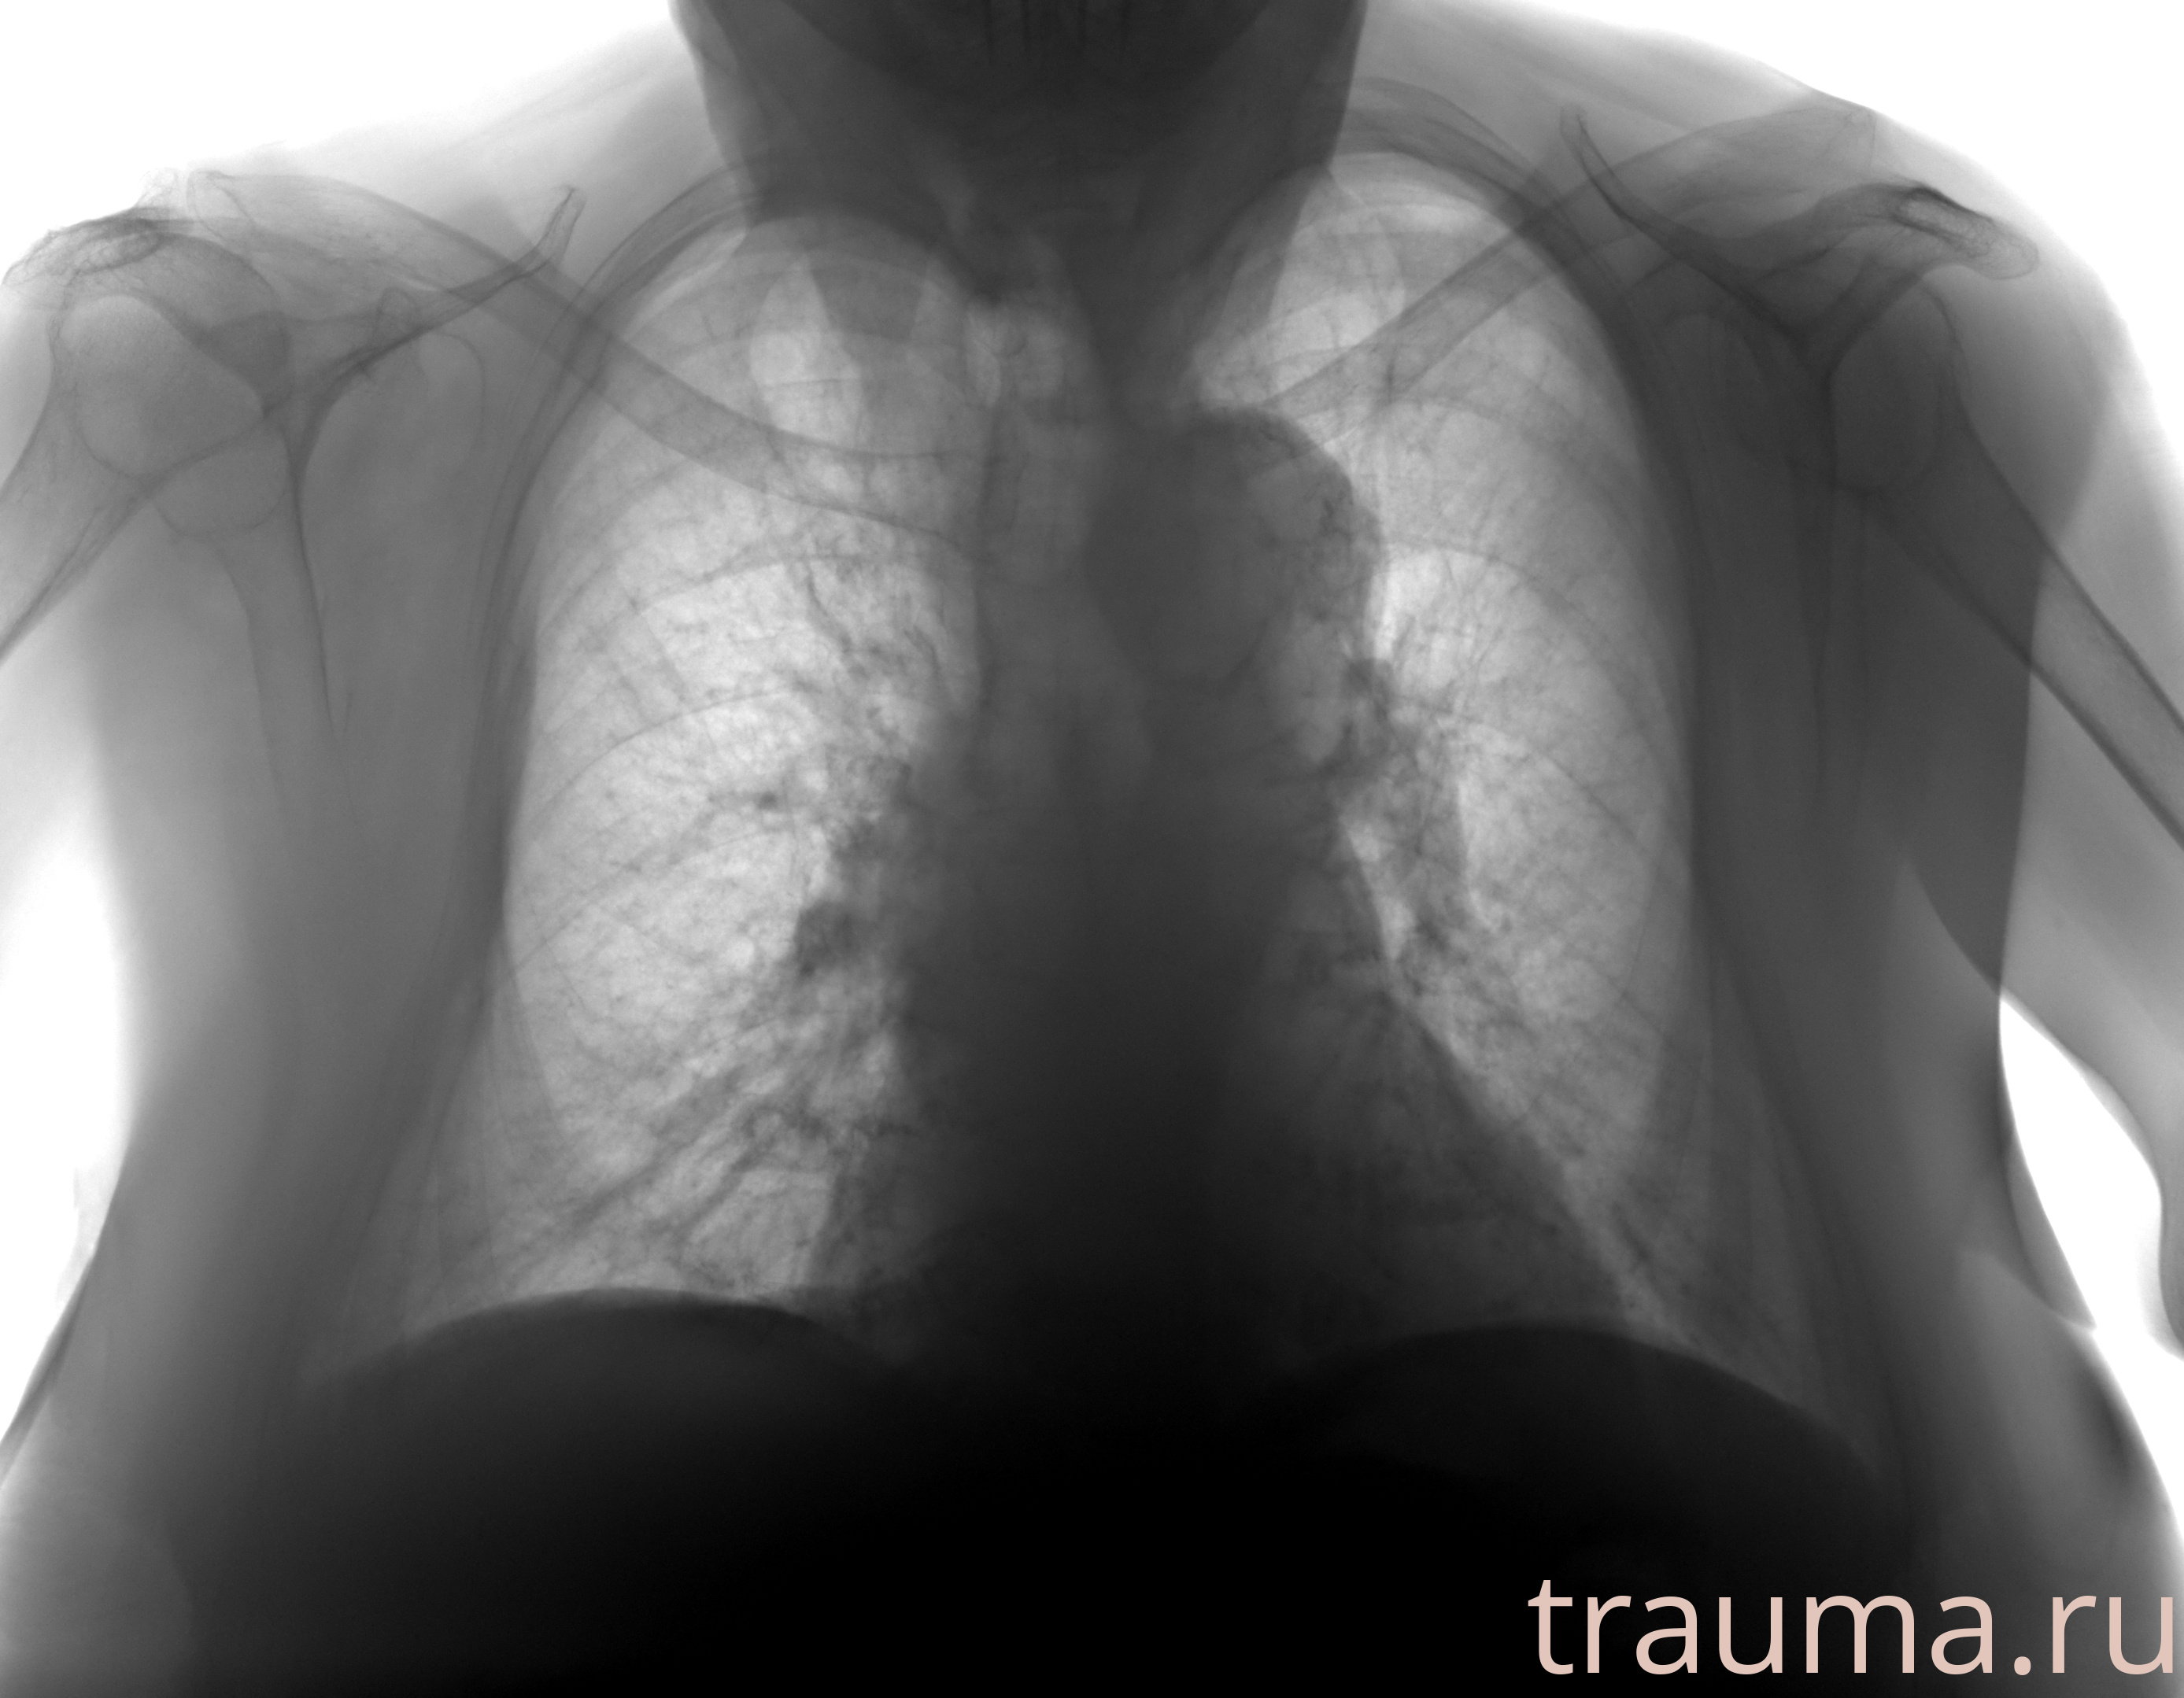

Рентген на дому: по вашему адресу приезжает врач-рентгенолог, травматолог-ортопед с мобильным рентгеновским аппаратом, проводит диагностику травмы или заболевания, делает необходимые рентгенограммы, дает рекомендации по дальнейшему лечению. Получить качественные снимки в домашних условиях возможно благодаря уникальной методике, разработанной МосРентген Центром для института  Склифосовского

при переломе шейки бедра и пневмонии от компании МосРентген Центр - партнера Института имени Склифосовского